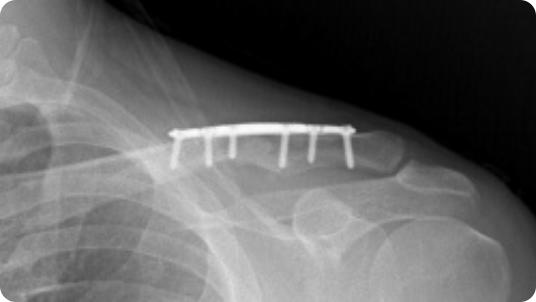

Radiographic image of a clavicle fracture Radiographic image of a clavicle ORIF (plate and screws)

Clavicle Fracture

Clavicle ORIF (Plate and Screws)